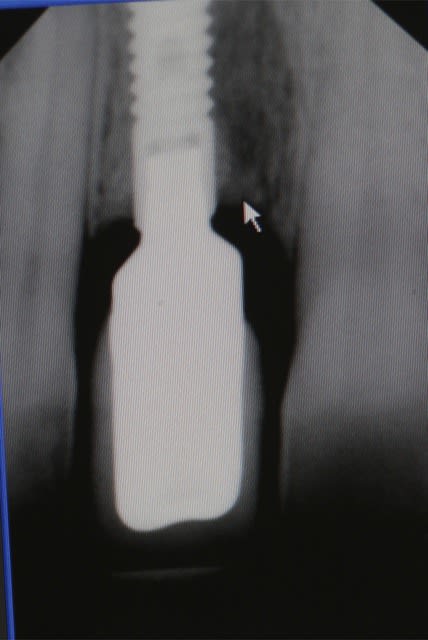

fig 1 coupe tomo Jo

fig 2 vue clinique ( léger décalage des collets entre 11 et 21 )

fig 3 exo

fig 4 pose membrane résorbable + os xénogène

fig 5 membrane suturée

fig 6 réouverture J0 + 6mois

fig 7 vue clinique J0 + 2ans ( Prothèse Dr G.D 31 )

fig 8 vue clinique JO + 5ans (léger décalage des collets entre 11 et 21 comme à l'origine)

fig 9 radio J0 + 5 ans